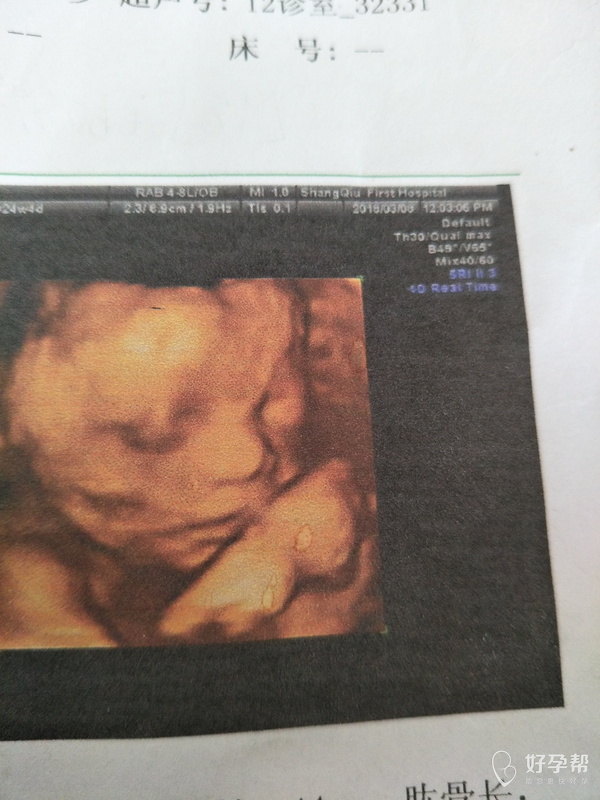

医生帮我看看这个四维图

检查结果还是可以的,不要担心,按时孕检